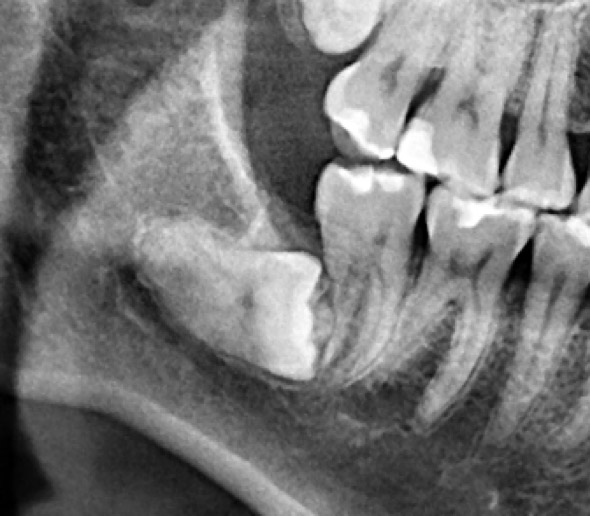

為了健保患者拔智齒的安全,遠離唇麻、舌麻、口鼻竇炎、大出血...等併發症,

☆本院特別巨資增設 ”千萬級3D AI透視電腦斷層”,並配合“成骨膠原蛋白”施作 (上述兩項目前健保無給付),讓您遠離神經傷害、口鼻竇(炎)相通...等併發症,除健保之外,難免會有避免併發症風險的自費項目,網路上經常會有看到智齒拔完後唇麻、舌麻、口鼻竇相通等併發症,在本院嚴格自我要求下,此類併發症在本院幾乎趨近於零。

外面拔完時常術後唇麻舌麻,本院發生趨近於零